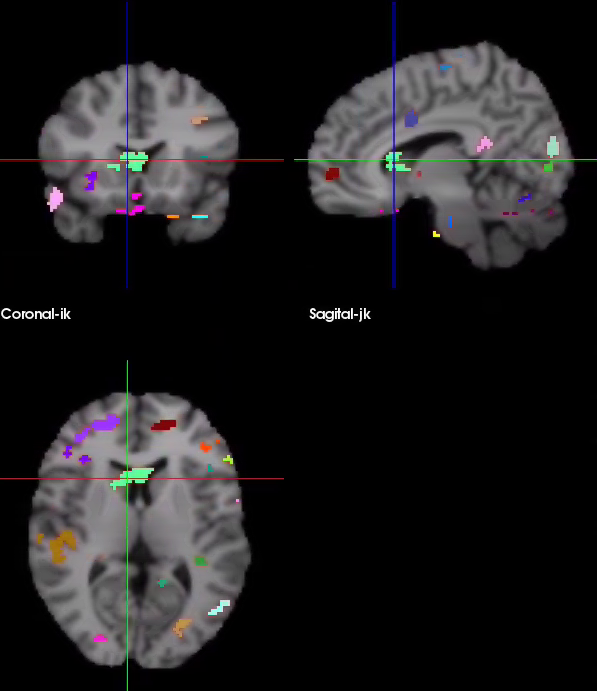

Is there a way to get different clusters in a same niftii file to be colored differently? I'm attaching what that looks like in bioimagesuite.